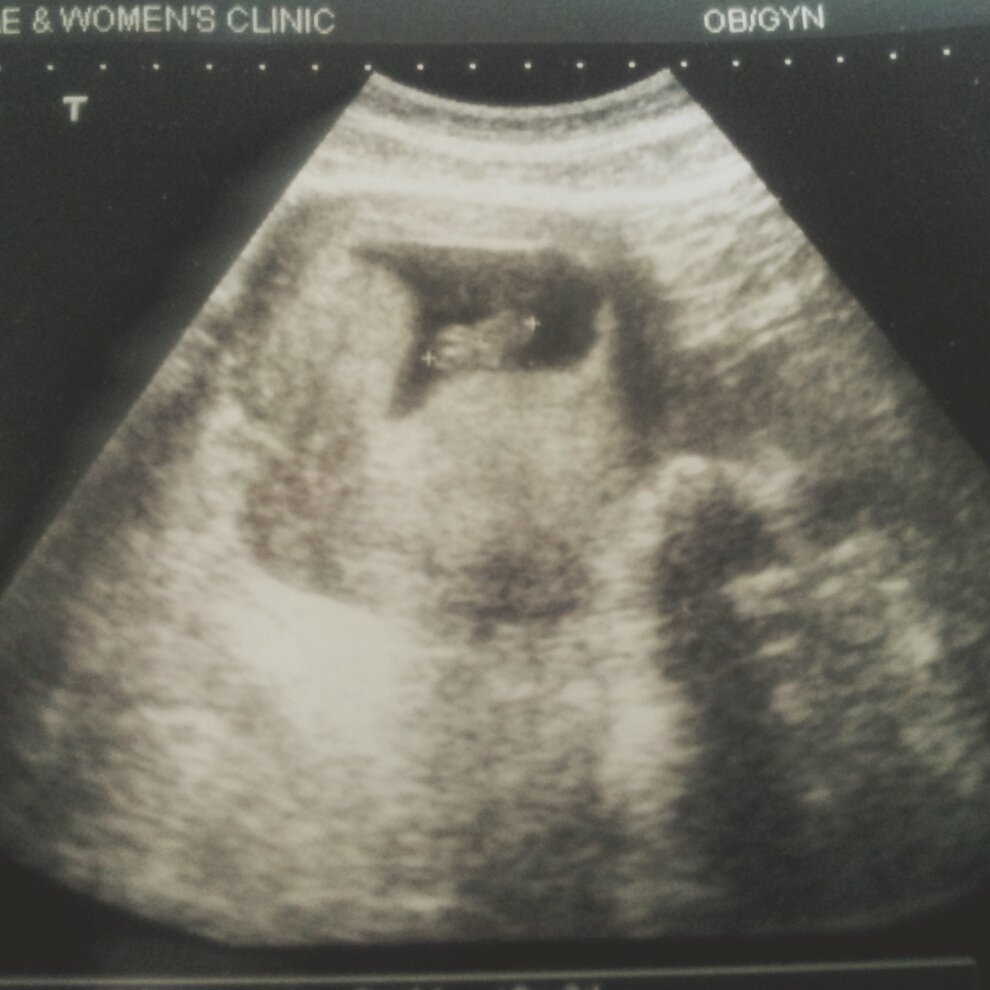

임신하면서 마음의 준비보단 몸이 더 먼저 느껴버린 엄마라는 타이틀.

그렇게 나는 뱃속의 아이가 크면서 빠르게 엄마가 되어가고 있었다.